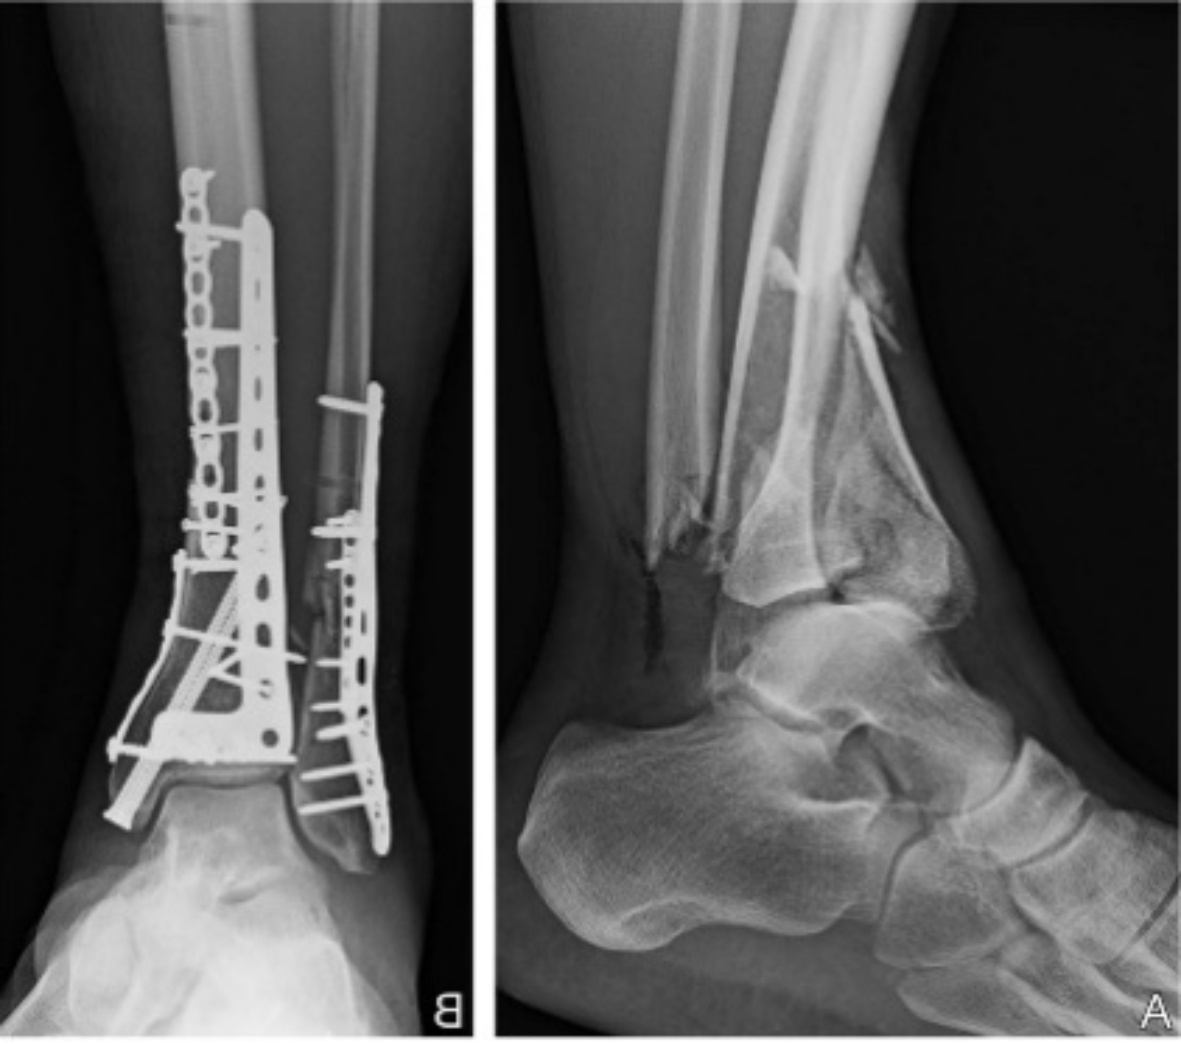

因此,医生们逐渐开始分阶段治疗Pilon骨折(见图1)。一期通过跟骨牵引、外固定架暂时固定Pilon骨折(见图2),恢复肢体长度和力线,避免早期切开加重软组织损伤(如伤口感染、皮瓣坏死等),开放性骨折或感染风险高的还可联合应用VSD;待软组织恢复后,二期再行骨折的解剖复位和接骨板固定(见图3) [5]。研究显示,通过分阶段治疗,并发症率从传统治疗的40%降至10%~15%,延期手术组的功能恢复优良率(85%)显著高于早期手术组(65%) [5]

Figure 1. Pilon fracture

1. Pilon骨折

Figure 2. External fixation

2. 外支架固定

Figure 3. Internal fixation

3. 内固定